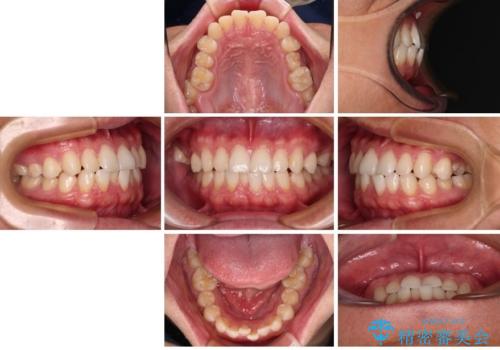

今回ご紹介するのは、「前歯のガタガタ(叢生)」と「奥歯のかみ合わせ(シザーズバイト)」にお悩みでご来院された患者様の症例です。

・上顎左右の第二大臼歯が頬側へ転移し、シザーズバイト(scissors bite)の状態

・上顎左側第二小臼歯が90度捻転しており、噛み合わせに影響

**前歯のデコボコ(叢生)**が整い、歯列全体が美しく改善

シザーズバイトの奥歯も正常なかみ合わせに改善

捻転歯も回転が修正され、全体的に清掃性・咀嚼効率が向上

患者様にも「大人になってから矯正を始めることに不安もありましたが、思っていたよりも短期間で治療が終わって本当にうれしいです。前歯のガタガタも気にならなくなり、笑うことに自信が持てるようになりました!」と喜んでいただけました。